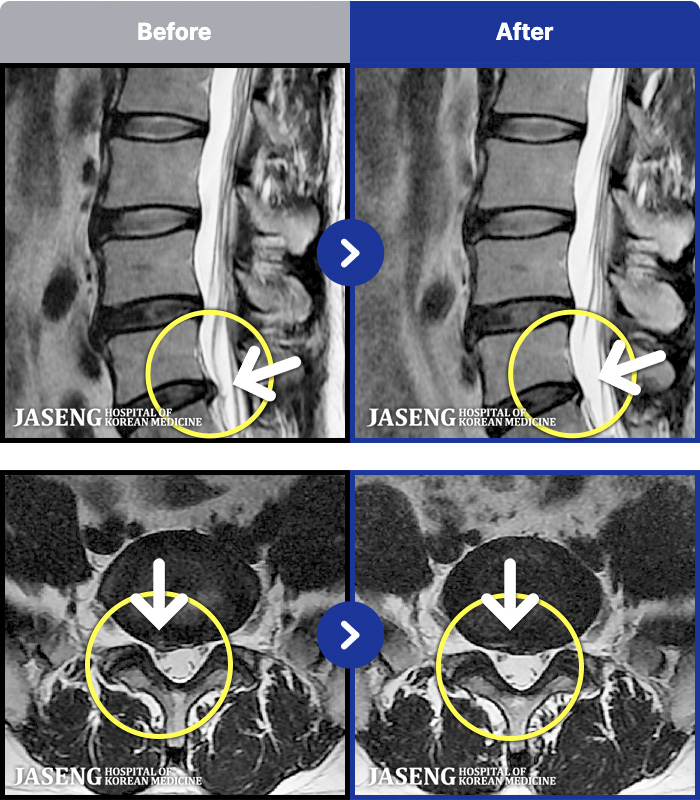

- MRI ġ

MRI ġ

1,299 MRI ũ ʸ Ȯϼ.